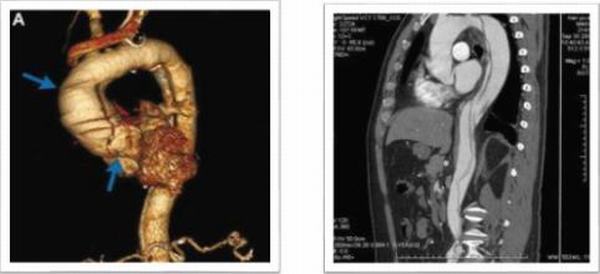

第一例患者31岁女性,运动员,有外伤史;主诉“反复胸痛2月,加重1小时”入院,入院后行主动脉CTA提示:升主动脉增宽,最宽处10.7cm,升主动脉近主动脉根部多发破口,最大破口直径5.1cm,最小破口直径0.64cm,主动脉夹层动脉瘤(A型)。心脏彩超:主动脉夹层(A型)伴主动脉瓣关闭不全,EF 50%,真腔内血流进入假腔,主动脉瓣反流(大量)。心肌损伤标志物正常,行术中探查破口累及主动脉弓部及降部,手术方案:升主动脉人工血管置换、主动脉弓置换、降主动脉支架植入、主动脉瓣机械瓣膜置换手术顺,利,术后第二天拔除气管插管,第12天出院。

第二例患者36岁男性,职员,马凡氏综合症;主诉“后背部疼痛3小时”入院,8年前因“马凡氏综合征、升主动脉瘤并主动脉伴关闭不全”在我科行Bentall手术;入院后行主动脉CTA提示:主动脉夹层动脉瘤(B型)合并主动脉弓瘤样扩张,直径7.0cm,主动脉弓至左髂总动脉双腔影,内膜片撕裂,并见多发破口,左侧锁骨下动脉起始部受累,破口内径约0.83-1.28cm,腹腔干起自真假腔,肠系膜上动脉假腔;左肾动脉起自假腔,右肾动脉起自真假腔;该病例为二次手术患者,且为夹层动脉瘤伴弓部瘤样扩张。拟行全主动脉弓置换、降主动脉支架植入术,手术顺利,术后第二天拔除气管插管,第14天出院,恢复良好。

第三例患者59岁男性,农民,有“腹部疼痛7小时,右下肢麻木5小时”入院,既往患有高血压病10余年,脑出血病史8年;在当地县医院行胸部增强CT提示:主动脉夹层动脉瘤(A型);救护车急诊送来我院,急查主动脉CTA:主动脉夹层I型(主动脉全程受累及)。心脏彩超:主动脉夹层动脉瘤(I型),主动脉瓣关闭不全,心包积液(少量),血流往返于真腔与假腔之间,主动脉瓣反流(大量)。该病例拟行Bentall、全主动脉弓置换、降主动脉支架植入术,手术顺利,术后第11天出院,恢复良好。